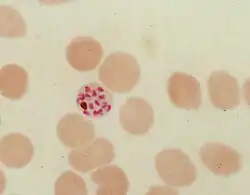

During its intraerythrocytic asexual reproduction cycle Plasmodium falciparum consumes up to 80% of the host cell hemoglobin.[8][9] The digestion of hemoglobin releases monomeric α-hematin (ferriprotoporphyrin IX). This compound is toxic, since it is a pro-oxidant and catalyzes the production of reactive oxygen species. Oxidative stress is believed to be generated during the conversion of heme (ferroprotoporphyrin) to hematin (ferriprotoporphyrin). Free hematin can also bind to and disrupt cell membranes, damaging cell structures and causing the lysis of the host erythrocyte.[10] The unique reactivity of this molecule has been demonstrated in several in vitro and in vivo experimental conditions.[11]

The malaria parasite, therefore, detoxifies the hematin, which it does by biocrystallization—converting it into insoluble and chemically inert β-hematin crystals (called hemozoin).[13][14][15] In Plasmodium the food vacuole fills with hemozoin crystals, which are about 100–200 nanometres long and each contain about 80,000 heme molecules.[4] Detoxification through biocrystallization is distinct from the detoxification process in mammals, where an enzyme called heme oxygenase instead breaks excess heme into biliverdin, iron, and carbon monoxide.[16]